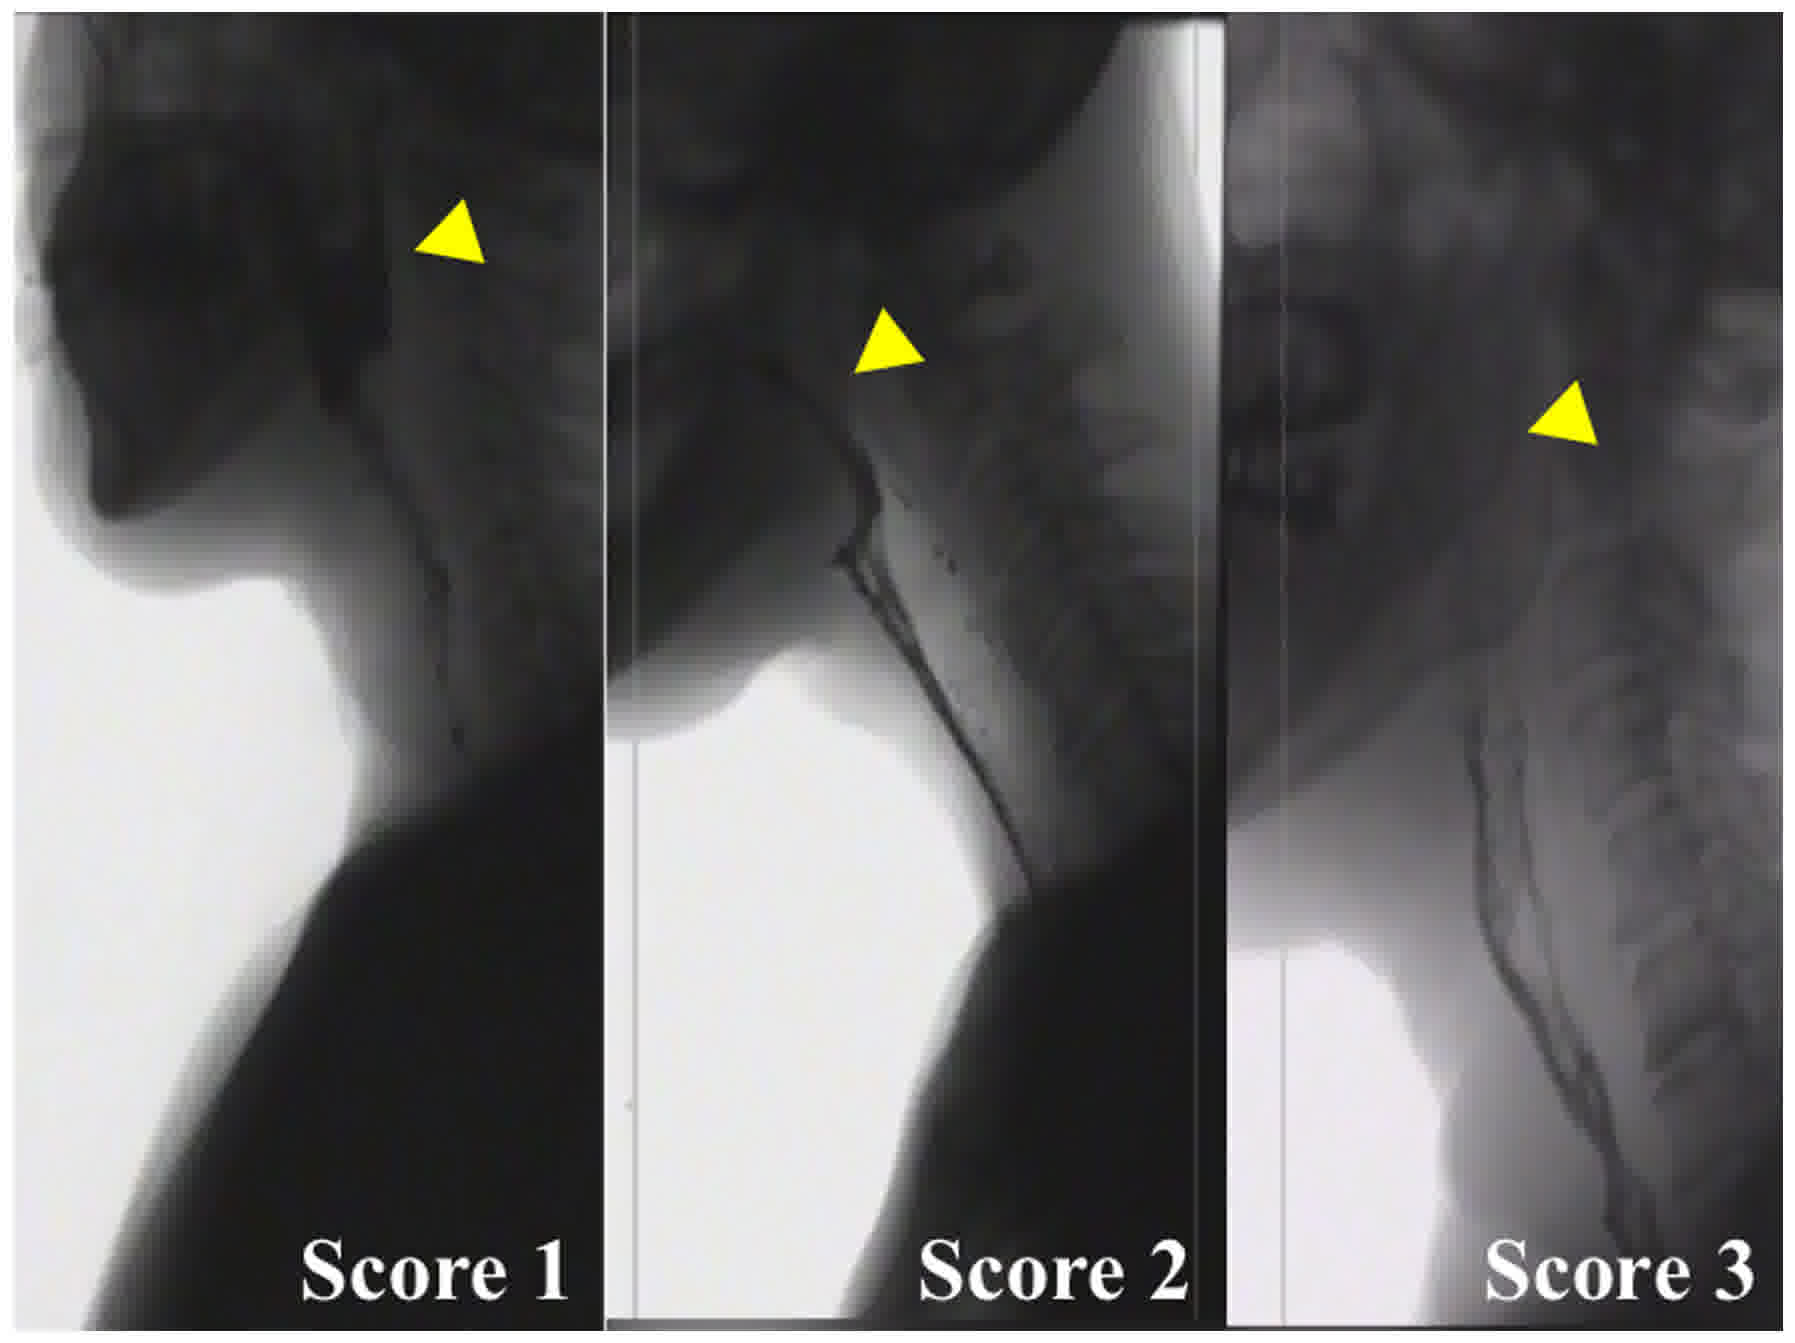

For recurrent cases or residual cases following concomitant chemo‑radiation therapy (CCRT), salvage surgery is a frequently used treatment options. A swallowing disorder is one of the major complications of CCRT. The purpose of the present study was to evaluate the effect of CCRT on swallowing function in patients who underwent salvage total pharyngo-laryngo-esophagectomy (TPLE), and to evaluate the importance of pharyngeal constriction in patients who underwent TPLE. Between 2008 January and 2014 May, 54 patients were treated with salvage TPLE following CCRT or TPLE at the National Cancer Center Hospital East, Chiba, Japan and were included in the present study. A total of 14 patients underwent salvage TPLE following CCRT for recurrence or residual tumor (the salvage TPLE group), and 40 patients underwent TPLE as initial treatment (the TPLE group). The pharyngeal constriction score and the post‑swallowing oropharyngeal residue rate were evaluated, and inadequate velopharyngeal closure was assessed by videofluorography. The pharyngeal constriction score of the salvage TPLE group was poorer than that of the TPLE group (P<0.05). The bolus residue in the oropharynx was significantly larger in the salvage TPLE group than in the TPLE group (P<0.05). With regards to inadequate velopharyngeal closure, there was no significant difference between the TPLE group and the salvage TPLE group (P>0.99). The results of the present study indicate that the swallowing function of patients who undergo salvage TPLE may be affected by CCRT.